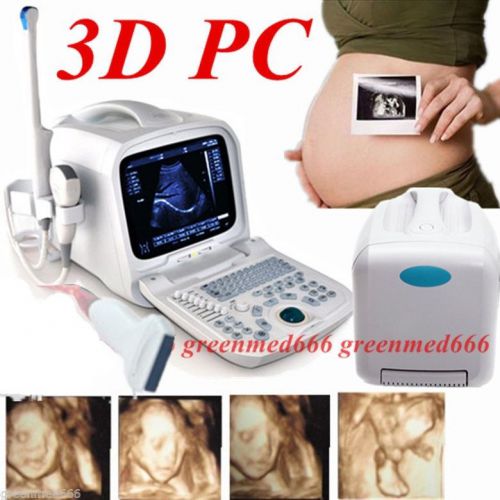

| Model | RUS-9000F |

3D PC platform Full Digital Portable Ultrasound Scanner + Transvaginal Probe FDA

3D PC Platform Full Digital Portable Ultrasound Scanner Machine +Convex Probe CE

3D PC platform Full Digital Portable Ultrasound Scanner +Transrectal Probe Human

3D PC platform Ultrasound Scanner +3.5MHz Convex &Transvaginal Probe Internet

3D PC platform Ultrasound Scanner +7.5MHz Linear &Transvaginal 2 Probes Internet